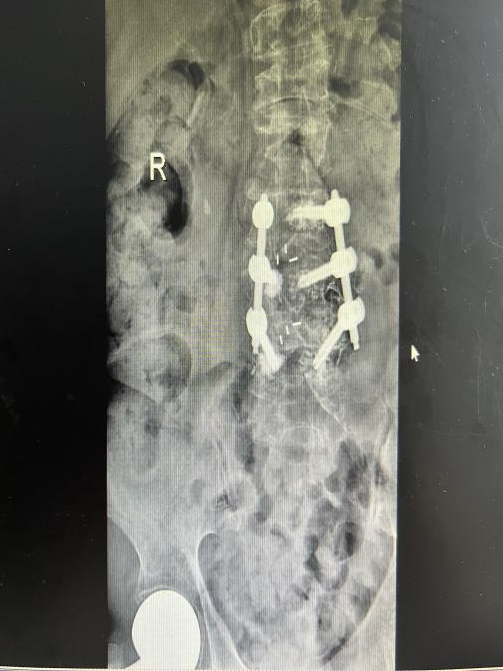

多年来,贵州航天医院各科室紧跟医学前沿,不断强技术、补短板,大力开展新技术、新项目,完成了许多高精尖、高难度、本地区“首例”的技术,填补了医院医疗技术空白,满足了群众日益增长的医疗需求。 贵州航天医院骨科率先在遵义地区开展骨搬移技术,截至目前,已治愈慢性骨髓炎、感染性骨不连、骨缺损、脉管炎、糖尿病足患者200余例,糖尿病足治疗保肢率达到98%。 本期,我们将为大家带来骨科特色技术——骨搬移技术(Ilizarov)。 案例分享 一名59岁的患者,身患糖尿病12年,在来我院3个月前出现了右脚溃烂的症状,来院就诊时,患者的右脚十分红肿,右脚脚趾坏死,伤口处不断流出黑红色脓液,情况十分严重。在接诊到患者时,骨科专家团队高度重视,立刻为患者完善了CT血管造影(CTA)等相关检查,诊断为:2型糖尿病,糖尿病周围血管病变,右糖尿病足。 术 前 考虑到患者情况比较严重,为最大限度保证患者肢体完整,科室专家团队进行了严格的讨论评估,为患者制定了骨搬移技术治疗方案,在征得患者及其家属的同意后,成功通过搬移骨块为患者进行治疗,促进患者病变肢体血管再生。 胫骨横向骨搬移外架固定 清除感染病灶 术后调节外架,通过搬移骨块 促进患肢血管再生 患者在术后三周前来换药,观察到感染得到进一步控制;术后六周复查,患者病变处已愈合,进行CT血管造影(CTA)后可明显观察到足部血管再生。 术后3周 术后6周愈合 CT血管造影见足部血管再生 糖尿病患者全身与局部的问题互为影响,形成恶性循环,糖尿病足溃疡创面迁延不愈,常见干性坏疽、湿性坏疽、趾坏死、深且大的溃疡以及骨髓炎等症状,还可导致脓毒血症,以往为保全生命,患者被迫选择一次或多次截肢。骨搬移技术的发展进步,能在血糖有效控制、局部有效清创下,有效促进患肢微血管再生,改善患肢血供,达到糖尿病足更快治疗康复的目的,并能根据病变情况最大限度的保障患者肢体完整。 什么是骨搬移技术 骨搬移技术是通过使用专用的骨外固定器固定骨段,每天缓慢牵拉,在牵拉搬移过程中,骨段尾部形成新骨及新的软组织,从而修复骨骼缺损及软组织缺损。是治疗大段骨缺损、骨不连、骨感染、肢体畸形的金标准方法,也用于治疗脉管炎、糖尿病足等肢体缺血性疾病。 骨感染缺损 切除感染段 搬移骨段 新骨形成 骨感染根治愈合 骨搬移技术原理 生物组织在持续、稳定、缓慢牵拉下,能刺激细胞分裂、组织再生,骨外固定技术运用该原理,通过持续缓慢调节外固定器形成牵拉张力,促进牵引成骨与相邻组织再生,如神经、血管、肌肉、皮肤等再生,达到治疗大段骨缺损、肢体缺血如糖尿病足等疾病的目的。 骨搬移技术优势 (一)除治疗骨缺损、骨不连外,有更广的适用范围,利用组织再生、血管再生等特性,能大量运用于肢体畸形的矫形、糖尿病足等的治疗。 (二)治疗效果确切,重建肢体外型和功能,极大降低截肢率和残疾率。 (三)明显提高了患者生活质量,极大减轻其家庭及社会负担。 肢体畸形的矫形 慢性骨髓炎 骨段切除 术后1年 濒临截肢的脉管炎术后6周 难愈创面术后3周 贵州航天医院骨科 专家团队 赵学平 骨科主任 主任医师 临床擅长:从事骨科临床工作30余年,对骨科常见疾病的诊治具有丰富的临床经验。 世界中医药联合会脊柱康复专业委员会常务理事,中华中医药学会整脊分会常务委员,中国中西医结合学会骨伤科分会肢体矫形功能重建与康复专家委员会常务委员,中国研究性医院学会骨科创新与转换专业委员会关节外科学组保髋工作委员会常委,中国康复技术转化及发展促进会骨外科与康复技术转化专业委员会常务委员,泛珠三角区域运动医学联盟(PPRD-SMA)理事会常务理事,中国研究型医院学会运动医学专业委员会委员,贵州省中医药学会整脊分会副主任委员,贵州省中西医结合学会银质针专业委员会副主任委员,贵州省康复医学会骨与关节专业委员会常务委员,贵州省人民医院骨科专科联盟常务理事,贵州省康复医学会骨内科专业委员会常务委员,中华医学会贵州省骨科学会委员,贵州省康复医学会脊柱脊髓专业委员会常务委员,贵州省运动医学分会委员,贵州省康复医学会骨与软组织肿瘤专业委员会委员,遵义市医学会创伤分会副主任委员,贵州省康复医学会骨内科专业委员会遵义地区分会常务委员,遵义市医疗事故鉴定、伤残鉴定、工伤鉴定、司法鉴定专家。 长期从事骨科临床研究及教学工作,在国家级、省部级杂志发表论文20余篇,SCI论文2篇,参与主编骨科专著2部,主持省部级科研项目2项,参与指导省部级、市级科研项目6项。 陈明勇 骨科副主任 副主任医师 临床擅长:从事创伤骨科工作约20年,对骨缺损、骨不连、骨肿瘤、肢体畸形等的肢体矫形重建及功能重建,慢性化脓性骨髓炎的根治治疗、糖尿病足的保肢治疗、快速康复理念(ERAS)下的老年骨折的诊治,四肢复杂骨折的诊治,四肢骨折等微创手术治疗具有丰富的临床经验。 2004年毕业于遵义医学院临床专业,曾在中国人民解放军总医院、广西医科大学第一附属医院、上海第六人民医院骨科进修。中国中西医结合学会骨伤科专业委员会横向骨搬移治疗糖尿病足及微血管网再生学组首届委员,遵义市医学会创伤分会常务委员。 瞿 辉 骨科 副主任医师 临床擅长:对骨科的常见病、关节外科、脊柱外科及运动医学疾病的诊治具有丰富的临床经验,熟练掌握骨科手术操作技术。 毕业于遵义医学院临床医学系,2005年前往广州中山大学第一附院骨显微医学部进修学习,2011年前往成都华西医院进修学习,并多次在省内外学习骨科相关知识,是中华医学会骨科分会会员。 赵兴东 骨科 主任医师 临床擅长:擅长骨科的常见病及各种创伤、四肢骨折创伤修复、骨感染、手足疾病的诊治和手足体表畸形的矫形整复,熟练掌握骨科四肢骨病及创伤的手术操作技术,尤其在四肢关节复杂性损伤、手足外伤、组织缺损创面、难治创面的皮瓣修复方面及平足、高弓足矫形方面及四肢慢性疼痛诊治、康复方面具有丰富的临床经验。 硕士研究生,毕业于遵义医学院临床外科系,2015年前往山东省立医院手足外科进修学习;遵义市医学分会创伤分会第一、二届委员,遵义市手外科医学会第二委届员会常务委员;在省级及省级以上期刊发表文章9篇,参编著作2部,参与主持并完成市级课题1项,参与市级课题2项、省级课题1项。 张俊凯 骨科 副主任医师 临床擅长:从事骨科临床工作28年,对创伤骨折、骨感染、骨缺损、骨不连等外科诊治,四肢骨折的微创手术治疗,四肢复杂骨折(如关节内粉碎性骨折、多发骨折等)的损伤控制及手术治疗等具有丰富的临床经验。 1995年毕业于遵义医学院临床专业,2009年前往复旦大学附属医院骨科进修1年。 卢懿明 骨科 副主任医师 临床擅长:从事骨科工作18年,对创伤骨折、四肢骨折的微创手术治疗、四肢复杂骨折(如关节内粉碎性骨折、多发骨折等)的损伤控制及手术治疗,尤其是髋部骨折的PFNA等微创技术,踝关节骨折、膝关节周围骨折的Mipo微创技术等具有丰富的临床经验,开展了4项新技术,发明6项新型专利技术。 2005年毕业于遵义医学院临床专业,2017年,前往南方医科大学第三附属医院骨科进修半年,回院后运用Mipo技术对骨干骨折及干骺端骨折的治疗技术,同时积极开展骨盆骨折、髋臼骨折腹直肌外侧切口的应用;发表了多篇专业论文,经常参与省内外学术交流会授课,获得医院荣誉称号多个。 邬夏荣 骨科 副主任医师 临床擅长:从事骨科工作16年,对四肢复杂骨折、骨肿瘤的诊治,尤其是足踝创伤、慢性踝关节损伤、平足症等诊疗具有丰富的临床经验。 2006年毕业于遵义医科大学临床医学专业,曾在陆军军医大学西南医院进修学习,发表多篇骨科学术论文。 余德怀 骨科 副主任医师 临床擅长:从事骨科工作10余年,对运动医学、骨关节、脊柱外科常见病、多发病的诊治具有丰富的临床经验。 硕士研究生,2011年毕业于遵义医学院临床医学专业,曾前往遵义医科大学附属医院运动医学专业进修学习;是贵州省医学会运动医学分会青年委员,西部关节镜联盟委员;发表多篇骨科学术论文。 冯 乾 骨科 副主任医师 临床擅长:从事骨科工作近20年,熟练掌握骨科多发病及常见病的诊治,尤其对脊柱退变性疾病的诊断及治疗具有丰富的临床经验,主要研究脊柱微创相关治疗方式,能熟练开展椎间孔镜及VBE。 曾前往北京大学第三医院进修学习疼痛及椎间孔镜、首都医科大学友谊医院专业进修脊柱内镜;是贵州省康复医学会第三届脊柱脊髓专业委员会委员;发明专利3项、发表脊柱外科专业论文多篇。 张艳金 骨科 副主任医师 临床擅长:从事骨外科工作16年,对复合伤、多发伤的救治、四肢骨干骨折、关节周围骨折、骨肿瘤、骨髓炎等诊治具有丰富的临床经验。 中共党员,硕士研究生,2006年本科毕业于山西医科大学第二临床医学院,2011年研究生毕业于北京军区总医院;在“老年COPD患者合并髋部骨折的诊治”国际合作课题组研究两年,在老年髋部骨折的诊治方面具有丰富的经验,并发表论文6篇;承担遵义市级课题1项;承担遵义医科大学的临床教学工作,获得遵义医科大学优秀带教老师荣誉。编撰有《骨科疾病诊疗精粹》一书,开展2项新技术,编撰地方规范《务川自治县创伤骨科常见疾病诊疗规范》一书。 赵小锋 骨科 副主任医师 临床擅长:从事骨科临床工作11年,对骨科常见病、多发病诊疗有较为丰富的临床经验,擅长脊柱相关疾病诊断及治疗,尤其是颈、腰、腿疼痛疾病诊断及治疗,擅长胸腰椎骨折微创经皮穿刺内固定术、经皮穿刺椎体成形术、经皮穿刺脊柱内镜下腰椎间盘摘除术、单纯开创腰椎间盘摘除术、腰椎滑脱复位椎间植骨椎融合内固定术、腰椎管狭窄减压融合内固定术及人工髋、膝关节置换术等。 2012年毕业于遵义医学院外科学专业硕士研究生,2019年参加“遵义市115医学人才精英计划”于上海交通大学第一附属医院培训学习,2023年于北京大学第三人民医院脊柱外科进修学习,曾获得遵义市优秀医师荣誉称号。 遵义市手外科第一届委员,遵义市医学会创伤分会第一届委员,遵义市医学会创伤分会第二届委员,贵州省康复医学会第三届脊柱脊髓专业会委员,遵义市医学会烧伤与整形外科学分会委员,发表论文5篇,其中国家级核心期刊1篇,SCI论文1篇,主持市级课题1项并结题,参与市级课题2项。 贵州航天医院骨科简介 基本情况 贵州航天医院(原3417医院)骨科组建于1968年,前身是以创伤和断肢(断指)再植闻名于世的上海市第六人民医院骨科,中国断肢(断指)再植的奠基者、中科院院士陈仲伟等著名专家、学者多次莅临科室指导医疗、教,是贵州省最早拥有专业骨科技术科室之一,在70年代开展了贵州省首例断肢(断指)再植手术。组建50余年来,诊治患者已逾百万,挽救了无数的伤病员,成为了保障遵义地区人民群众健康的重要支撑。 经过几代人的不懈努力,今天的骨科,已由创伤骨科发展至骨病、骨肿瘤、骨结核等领域,现有脊柱外科、关节外科、四肢创伤、手足外科四个亚专科,成为了集医疗、教学、科研于一体的综合学科,是贵州省临床重点专科、遵义市临床重点专科、遵义市骨科临床医学中心、遵义市基层骨科专科联盟理事长单位。 科室目前开放床位110张,共有医护人员50余人,副高级以上专家18人,硕士研究生15人。拥有一流骨科医疗设备多台,每年不定期选派优秀技术骨干到全国各大知名医学院校进修、学习、参观、交流,并邀请国内、国外知名专家教授来院进行交流、指导,通过不断引进国内外先进的诊疗技术,科室医疗技术水平稳步提升,为广大人民群众提供了优质的医疗服务。 专科特色 骨一科 (一)骨缺损、骨不连的肢体与功能重建 胫骨横向骨搬移技术治疗糖尿病足: (二)慢性骨髓炎的根治治疗 (三)肢体缺血性疾病如糖尿病足、脉管炎的保肢治疗 (四)皮瓣修复 (五)复杂创伤的治疗 (六)老年髋部骨折及小儿骨折快速手术 老年髋部骨折: 骨二科 (一)胸腰椎骨折微创经皮椎弓根螺钉固定术 (二)老年性骨质疏松性患者腰椎滑脱脊柱内固定术(骨水泥螺钉) (三)V形双通道脊柱内镜技术(VBE)腰椎融合术治疗腰椎退行性疾病 (四)老年性骨质疏松性骨折(PVP/PKP)术 (五)人工髋关节置换术 (六)双侧股骨头坏死人工全髋关节置换 (七)右侧全髋置换术后假体周围骨折翻修 (八)人工膝关节置换术 (九)人工膝关节假体松动翻修 (十)关节镜技术 传统手术切口 关节镜技术切口 诊疗范围 骨一科 1.四肢创伤、矫形。 2.手、足踝外科。 骨二科